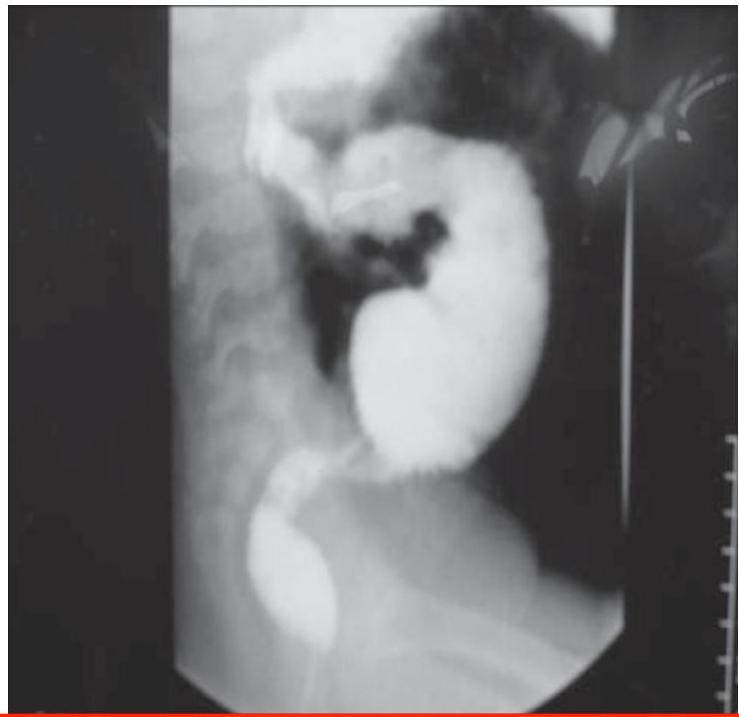

Intussusception

- 18 Months old boy presented with crying and vomiting.

- A bloody stool was passed on the day of the imaging examinations (classically described as “currant jelly” stool).

Diagnosis? Ileocolic intussusception.

Investigation? Barium enema.

Sign?

- Cut-off sign in the middle

- Coiled spring appearance / spring sign / target sign

Etiology:

- Idiopathic

- Secondary to: HSP, intestinal polyps

Emergency:

- Type of obstruction

Treatment:

- NPO/IV fluids

- NGT aspiration

- IV antibiotics

- Hydrostatic reduction with Barium/air enema

- Laparotomy and resection if needed

Complications:

- Ischemia and necrosis